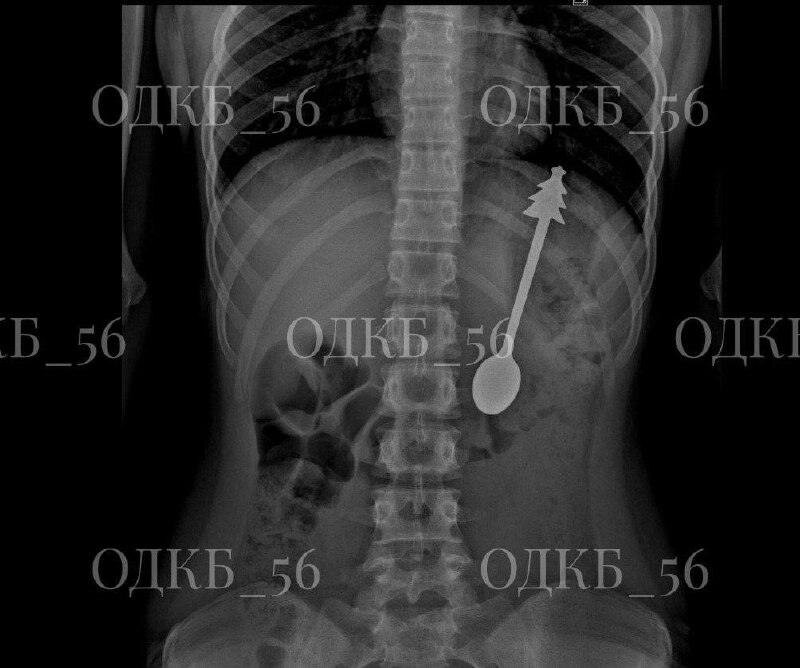

В Оренбурге ребёнок проглотил 14-сантиметровую ложку

В Оренбурге зафиксирован необычный медицинский случай: ребёнок проглотил ложку длиной 14 сантиметров. Инцидент произошёл в минувшие дни, подробности стали известны благодаря сообщениям местных СМИ.

Пациента оперативно доставили в областную детскую клиническую больницу. После проведения рентгенологического исследования врачи подтвердили наличие инородного предмета в желудке. Медики провели процедуру извлечения ложки, которая прошла без осложнений.

Уже на следующий день ребёнка выписали из медицинского учреждения. По словам врачей, его состояние оценивается как удовлетворительное. Подобные случаи, хотя и редки, требуют оперативного вмешательства специалистов для предотвращения возможных последствий.